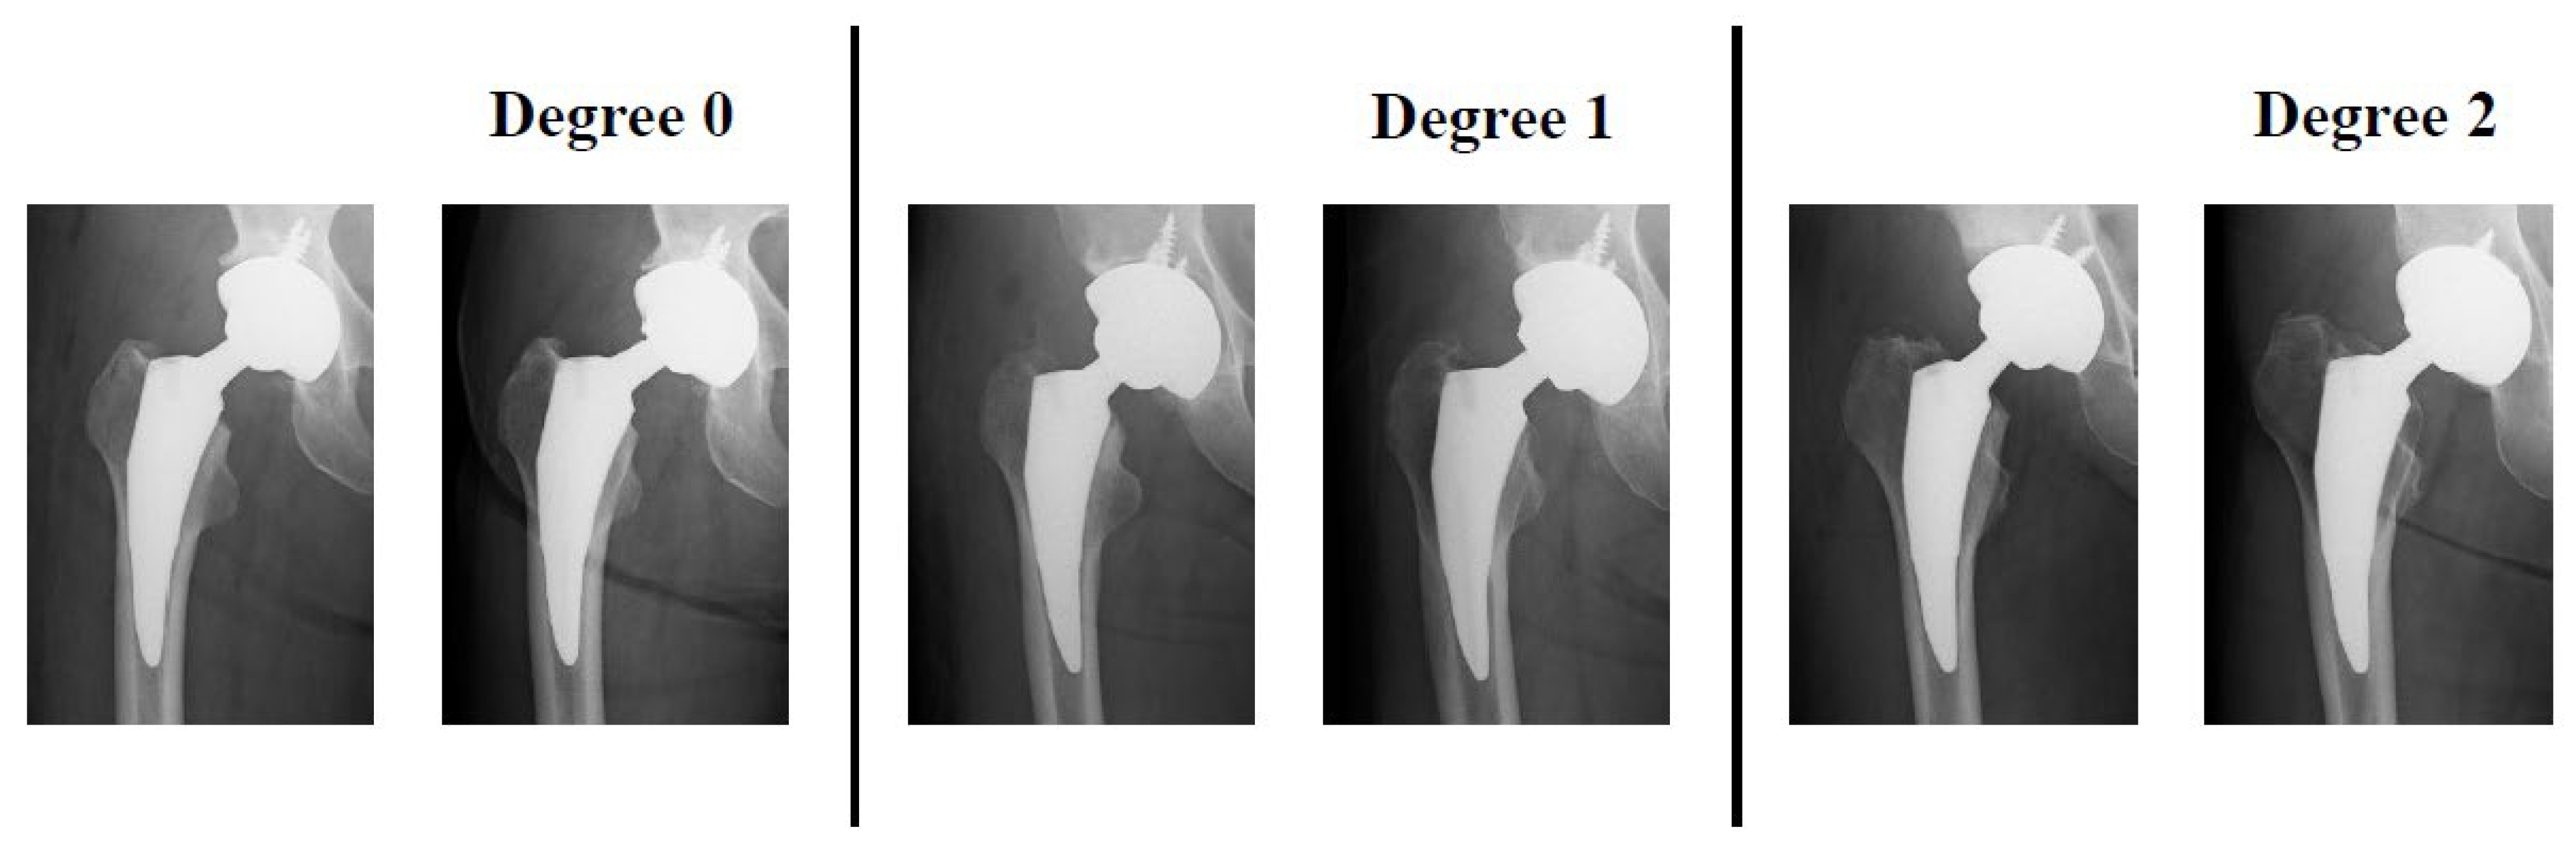

Engh's classification of stress shielding. Download Table Stress Shielding Radiology Hip Web the relationship between stress shielding and bone resorption around total hip stems and the effects of flexible. Web stress shielding refers to the transfer of the normal load from the femoral neck and intertrochanteric region to the. Relations between stress shielding and the clinical outcomes of total hip arthroplasty (tha) remain topics. Web complications of total hip arthroplasty are. Stress Shielding Radiology Hip.